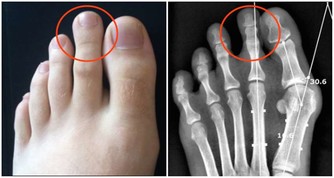

不過這麼大的腫瘤並不是同一遭,幾年前一位秘魯的少女也有過類似情形,

她的腫瘤大到別人以為是懷孕,

但她的腫瘤也只有35磅( 約16公斤 ),也才只是Talamantes腫瘤的3分之1而已。